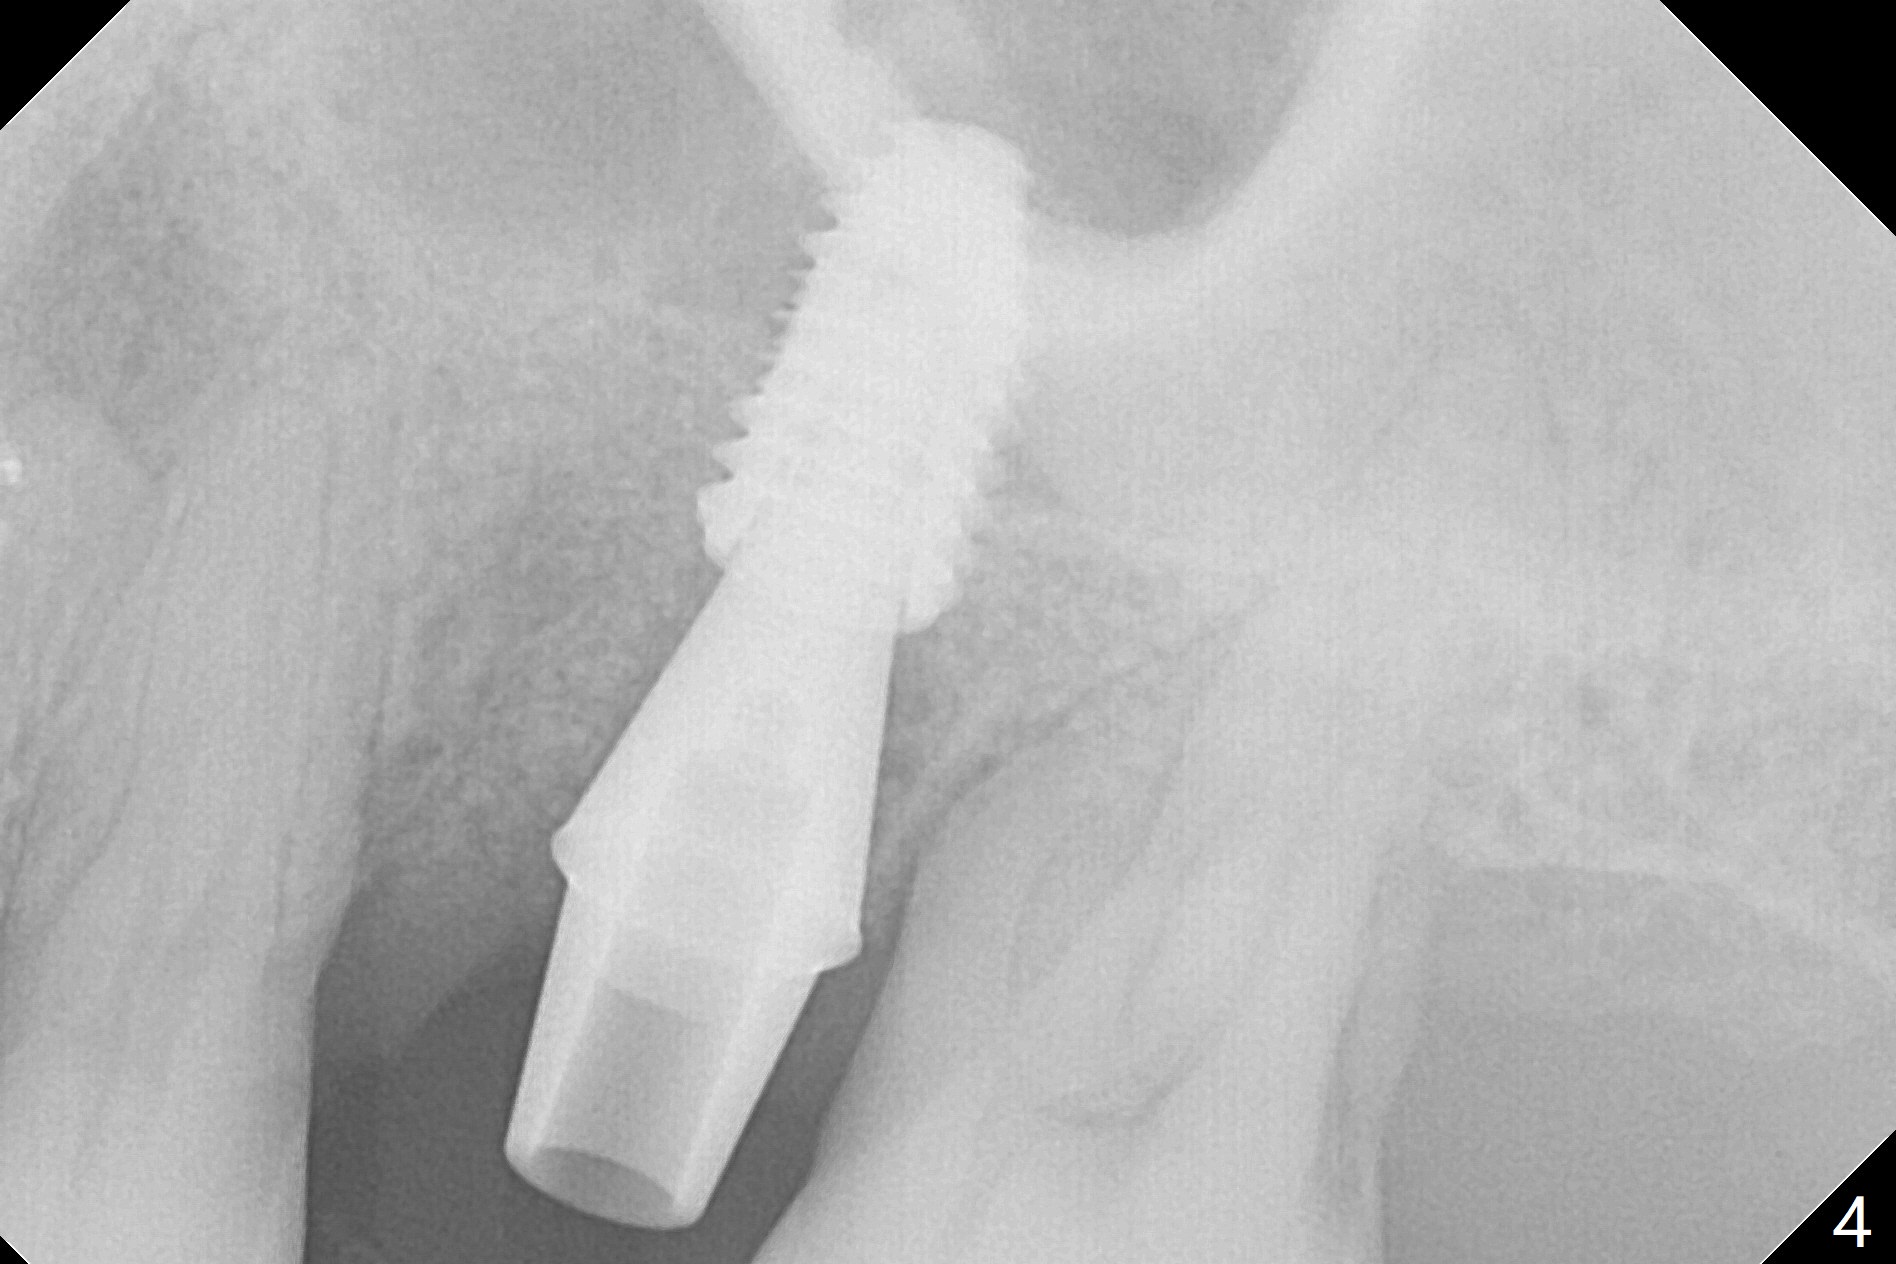

Six months post 2nd placement at #14, the 5x11 mm IBS implant is unstable. The patient smokes a cigarette a day.  After implant removal, the palatal wall of the osteotomy is intact, although low.  With removal of minimal granulation tissue, a 5x10 mm IS dummy implant is placed with stability and slightly subgingival palatal (Fig.1,2).  A 5x8.5 mm definitive implant is placed with ~ 40 Ncm and 3-4 mm subgingival palatal (Fig.3,4).  A 5.7x5.5(5) mm abutment is placed to hold periodontal dressing in place.  If the implant fails again, bone graft should be placed.  The abutment and implant are stable 4.5 months postop (Fig.5); a provisional is fabricated for progressive loading.  The provisional at #14 is narrow mesiodistally, while the tooth #15 is mesially tilted and shifted because of chronic periodontitis and 1 year 4 months of edentulism (Fig.6*).  Limited orthodontics is necessary prior to final restoration.  The 1st step is to raise the occlusion with #14 temporary reline (Fig.7 *); the tooth #15 is distalized initially with a separator, which is inefficient.  It appears that brackets and bands should be placed for distalization.  A month post banding, open coil spring is placed between #14 and 15; with occlusal composite on the opposing tooth (#19) (Fig.8), the tooth #15 is distalized instantly probably related to its periodontal condition (Fig.9 mirror view).  The tooth #15 is further distalized 2 weeks post open coil spring placement (Fig.10).  To act an anchorage, the abutment needs to be torqued with wrench (25-30 Ncm) and the provisional has to be permanently cemented.  The distalization appears to be ~ 1 mm shy 1.5 months post open coil (Fig.11).